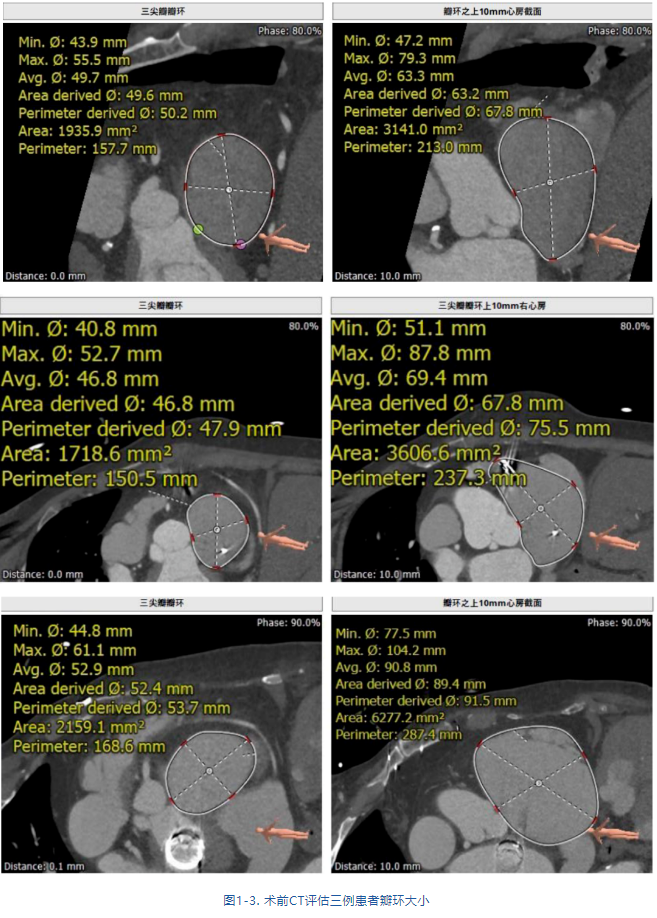

接受治療的是三例重度三尖瓣反流患者,術(shù)前基礎(chǔ)疾病多,均患有嚴(yán)重心律失常,其中兩例患者NYHA心功能Ⅱ/Ⅲ級。結(jié)合術(shù)前CT評估結(jié)果,三例患者的自體瓣環(huán)都較大(圖1-3),最大者平均瓣環(huán)為53.7mm;有一例患者有起搏器植入史,術(shù)中操作有纏繞起搏器導(dǎo)線的風(fēng)險;三例患者入路血管均無嚴(yán)重迂曲和鈣化。經(jīng)術(shù)前討論分析,潘湘斌教授及其團隊潘家華教授、朱達教授、王首正教授以及心超室的駱志玲教授,董念國教授及其團隊謝明星教授、尚小珂教授、陳澍教授、鐘禹成教授經(jīng)過討論決定,采用創(chuàng)新的 LuX-Valve Plus經(jīng)血管三尖瓣置換系統(tǒng)對患者進行手術(shù)。LuX-Valve Plus是我國自主研發(fā)的經(jīng)血管介入三尖瓣置換系統(tǒng),經(jīng)頸靜脈入路的微創(chuàng)方式可進一步降低對患者的創(chuàng)傷。